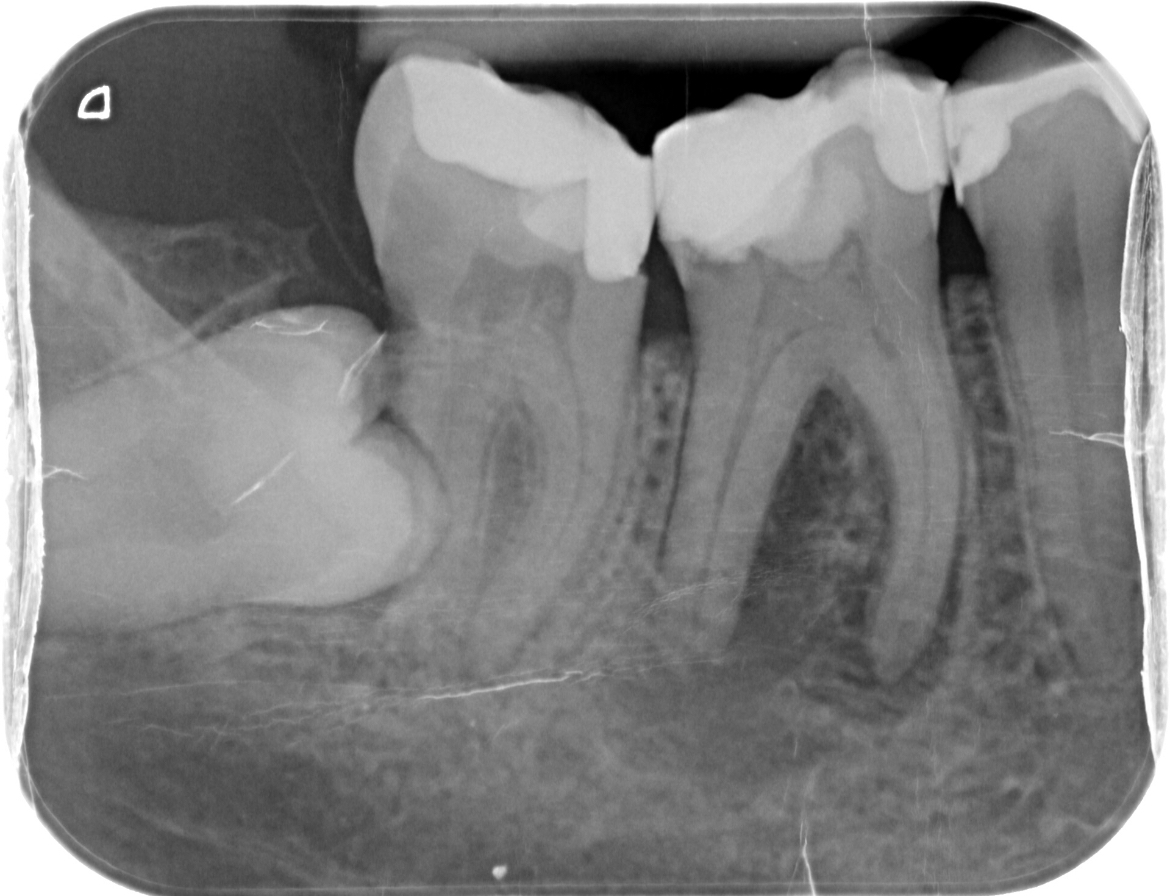

Wie kan mij helpen. Na lang uitstellen heb ik toch maar een afspraak gemaakt bij de kaakchirurg ingepland om mijn verstandskies eruit te halen die dwars ligt. (23 februari) De kiest daarnaast blijft staan en in de andere kies die daar naast staat zou een ontsteking zitten in de wortelpunt. Ik schrok heel erg van de kosten dus twijfel nu wat te doen. Of een wortelkanaalbehandeling of door de vele vullingen die al in deze tand zitten deze ook maar te trekken. Ik ben erg onzeker over mijn gebit door alle vullingen die ik heb in met name de kiezen. Aan de andere kant van mijn gebit is namelijk ook al een kies getrokken omdat deze gewoon heel zwak was en constant afbrak.

Ik hoop dat ik nog wel even met mijn tanden kan doen. Wat vind je op dit moment van de foto?

Je zou dus wel een wortelkanaalbehandeling doen ipv trekken (de eerste kies)

Zie je een grote ontsteking? Of kan dit nog behandeld worden met een antibiotica kuur.

Verstand kies verwijderen, wkb 46 ( eerste grote kies flinke ontsteking niet met AB kuur goed te krijgen) later kroon ( als u kiest voor behoud met vaste voorzieningen).....

Ik ben vanmorgen naar de kaakchirurg geweest. We moesten een nieuwe afspraak inplannen ivm de kies die in het kaakbot ligt. Graag uw mening over kies 46 aan dezelfde kant.

Kaakchirurg vind het lastig beoordelen en de tandarts ook. Ik heb geen pijn maar de kies is wel zwak en er zit een ontsteking (weet niet in welke staat de ontsteking is) kaakchirurg denkt dat trekken beter is uiteindelijk. Tandarts zegt wortelkanaalbehandeling proberen. Ik ben erg verdrietig over de situatie

U ziet wat er gebeurt als een kies getrokken wordt en niet wordt vervangen ( zie hoe links onder, 37, uitgegroeid is).

Er zijn ontstekingen aan de 46/ 33/ 34/ mogelijk 25 en gaatjes in de 15/ 14???/24??/25??/45?? moeilijk te zien op deze foto daar zou extra kleine foto's voor gemaakt moeten worden... Zwaar gevulde kiezen waar geen kronen op zijn gemaakt. Problemen met uw bot niveau ( voortanden boven). Roker??. Als u geen financiele middelen heeft zou ik in dit geval een frame prothese overwegen.

Uheeft een x-foto mee gestuurd. Daar heb ik op gereageerd met wat ik zie. Omdat ik de behandel strategie voor de toekomst niet weet heb ik een voorzet gegeven v een v d mogelijkheden (frame) en wat daarvoor nodig is, de zichtbare valkuilen.. Een frame indien de 46 getrokken wordt en geen WKB (duidelijk te zien op de eerste x-foto) gekozen wordt. Met dat advies kunt u doen wat u wilt.